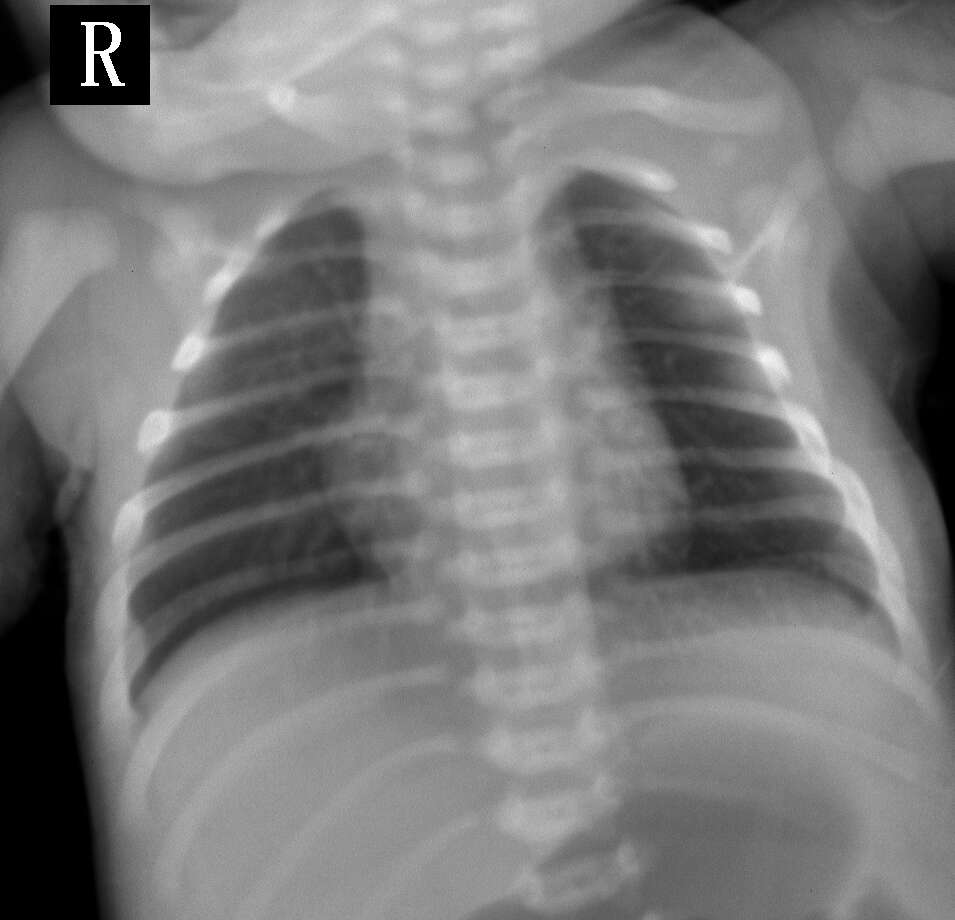

因为婴儿不能配合,影像有点模糊,患者3天,发作痰鸣,气促伴发绀,临床诊断:1、吸入性肺炎2、肺不张

肺纹理略增重,余(-)。

肺纹理稍强。

肺纹理略增重,建议结合临床

未见明显异常表现。可能为毛细支气管炎。